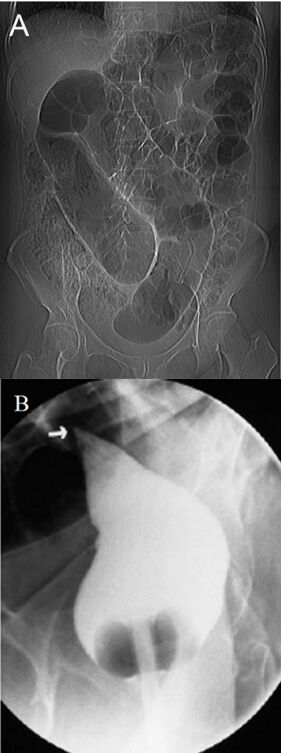

72.75歲老人由療養院送來,主訴腹脹,腹部X光片如圖(A),下消化道鋇劑攝影如圖(B),則其最可能的診斷為下列何者?(A)無力性腸阻塞(adynamic ileus)(B)上腸繫膜動脈症候群(superior mesenteric artery syndrome)(C)乙狀結腸扭轉(sigmoid volvulus) (D)近端腸環症候群(afferent loop syndrome)